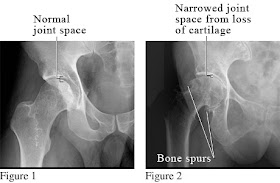

Radiological signs of osteoarthritis:

1-Irregular or asymmetric narrowing of the joint space.

2-Increased density of subchondral bone.

3-Formation of osteophytes.

4-Formation of pseudo-cyst in subchondral bone marrow